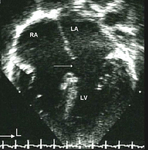

Imagen de ecocardiografía de 4 cámaras apical de una comunicación auriculoventricular (CAV) completa. Observe la comunicación interauricular (CIA) de tipo ostium primum (*) y la comunicación interventricular (CIV) de entrada contigua (flecha). (AD) aurícula derecha; (AI) aurícula izquierda; (VD) ventrículo derecho; (VI) ventrículo izquierdo

Imagen cortesía de Patrick W. O'Leary, MD